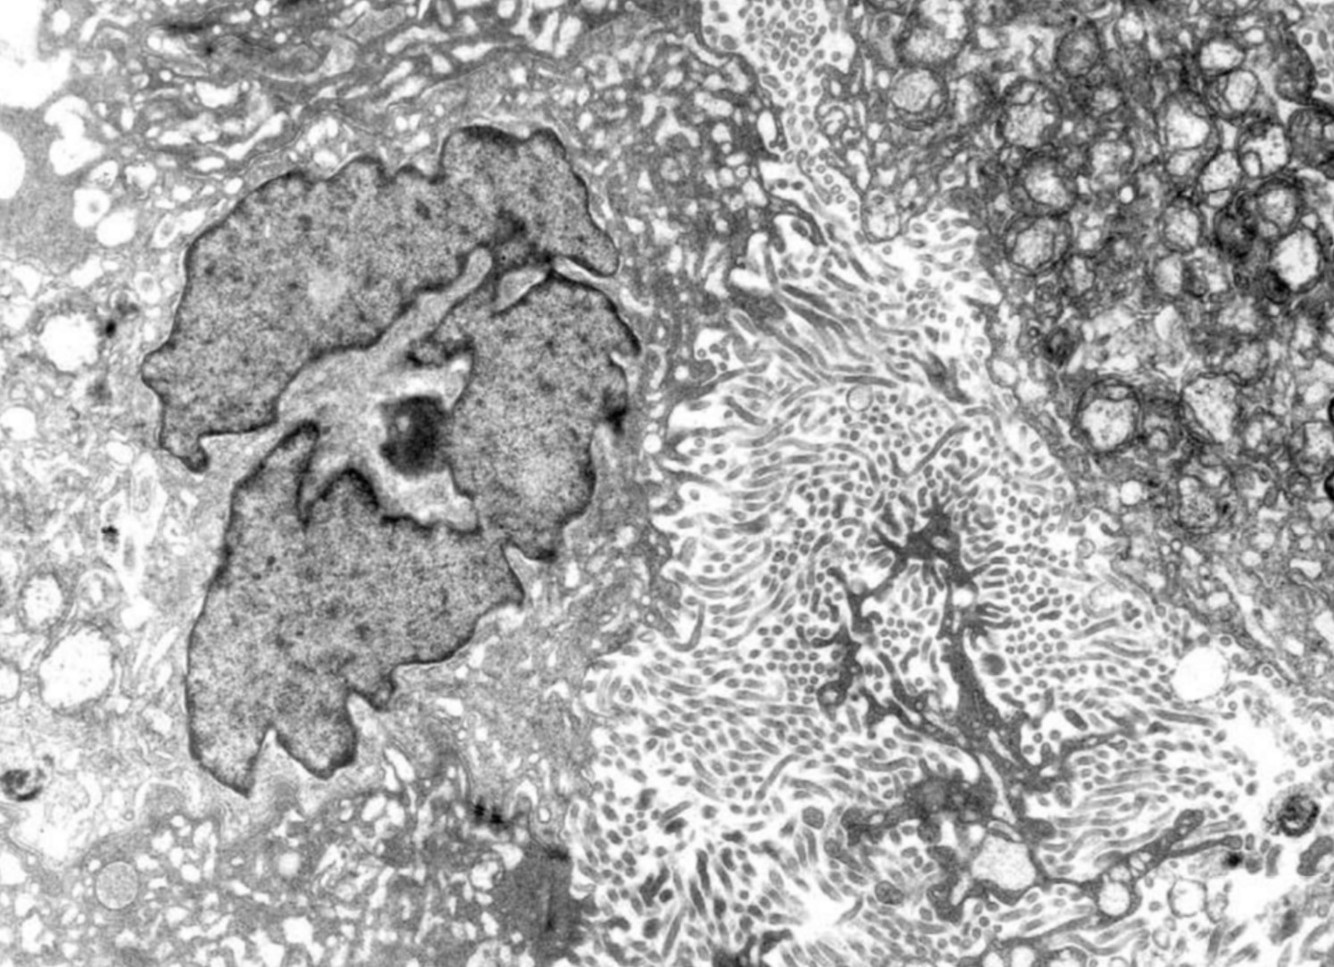

MESOTHELIOMA

• DIAGNOSTIC CRITERIA:

• LONG THIN MICROVILLI

• LENGTH:DIAMETER RATIO 10:1